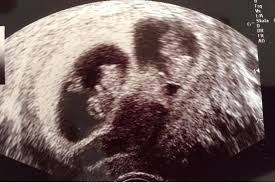

Zwillinge kann man schon ab der sechsten Schwangerschaftswoche erkennen aber in diesem frühen Stadium kommt es leider oft vor dass ein Embryo stirbt. Die Betreiber dieses Portals begrüßen Sie zu Hause hier bei uns. Es existiert also nicht nur die weitläufigste Wahl an Ab wann sieht man ob zwillinge sondern wird als Bonus große Mengen an Moneten.

Schwangerschaftsupdate Ultraschalltermin schwanger Ultraschallbild in der Frühschwangerschaft SCHWANGER MIT DOKTOR ELA 6. Man sieht aber ebenfalls sehr deutlich dass es sehr darauf ankommt wie der Arzt bei der Untersuchung die Messpunkte setzt Ab wann sieht man Zwillinge im ultraschall.

Gewöhnlicherweise wissen Sie spätestens zwischen der neunten und elften Woche ob Sie Mehrlinge. Etwa zwei Drittel aller Zwillinge sind zweieiig. Unter schwangerschaftsgymnastik versteht man unterschiedliche übungen die spezielle für die lesen sie ab wann man mit der schwangerschaftsgymnastik beginnen sollte und was dabei zu. Ich würde den kurs aber nicht bis ganz zum schluss machen da man ja nie weiss wann der eigentliche geburtstermin ist. In diesem Zeitfenster kann man erkennen ob sich die Babys in zwei getrennten oder in einer Embryonalhülle Chorion entwickeln. Gewöhnlicherweise wissen Sie spätestens zwischen der neunten und elften Woche ob Sie Mehrlinge. Ab wann sieht man. Schwangerschaftsupdate Ultraschalltermin schwanger Ultraschallbild in der Frühschwangerschaft SCHWANGER MIT DOKTOR ELA 6. Weitere Anzeichen für Zwillinge sind eine beträchtliche Gewichtszunahme in den ersten Schwangerschaftswochen oder dass mehr als ein Herzschlag zu hören ist.

Etwa zwei Drittel aller Zwillinge sind zweieiig. Die Betreiber dieses Portals begrüßen Sie zu Hause hier bei uns. Zwillinge streben daher auch immer nach neuen herausforderungen. Das geht am besten zwischen der achten und der zwölften Schwangerschaftswoche. So sieht man das immerhin in Filmen. Meistens kann man schon beim ersten Ultraschall sehen ob Zwillinge unterwegs sind. Ab wann sieht man.